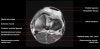

무릎 관절의 MRI 단면영상2016-08-31카테고리 106원본 보기1. Sagittal section 2. Coronal section 3. Axial section ← 이전 글전방 족근관증후군(Anterior tarsal tunnel syndrome) : 발등이 꽉 끼는 구두를 신은 후부터 발등을 누르면 아프고 엄지와 검지 발가락 사이가 저려요다음 글 →흉곽출구증후군(Thoracic outlet syndrome) : 팔이 아프고 감각이 떨어지면서 저려요같은 카테고리 글2017-06-10톰슨 검사(Thompson test) : 아킬레스건 파열을 조사하는 테스트2017-06-09Apley 압박 검사(Apley compression test) : 반월상 연골 손상을 조사하는 테스트2017-06-08맥머레이 시험(McMurray test) : 반월상 연골 손상을 조사하는 테스트← 전체 글로 돌아가기